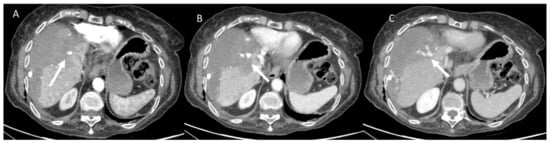

- Granata, V.; Petrillo, M.; Fusco, R.; Setola, S.V.; De Lutio Di Castelguidone, E.; Catalano, O.; Piccirillo, M.; Albino, V.; Izzo, F.; Petrillo, A. Surveillance of HCC Patients after Liver RFA: Role of MRI with Hepatospecific Contrast versus Three-Phase CT Scan—Experience of High Volume Oncologic Institute. Gastroenterol. Res. Pract. 2013, 2013, 469097. [Google Scholar] [CrossRef]

- Granata, V.; Grassi, R.; Fusco, R.; Setola, S.; Belli, A.; Piccirillo, M.; Pradella, S.; Giordano, M.; Cappabianca, S.; Brunese, L.; et al. Abbreviated MRI Protocol for the Assessment of Ablated Area in HCC Patients. Int. J. Environ. Res. Public Health 2021, 18, 3598. [Google Scholar] [CrossRef]